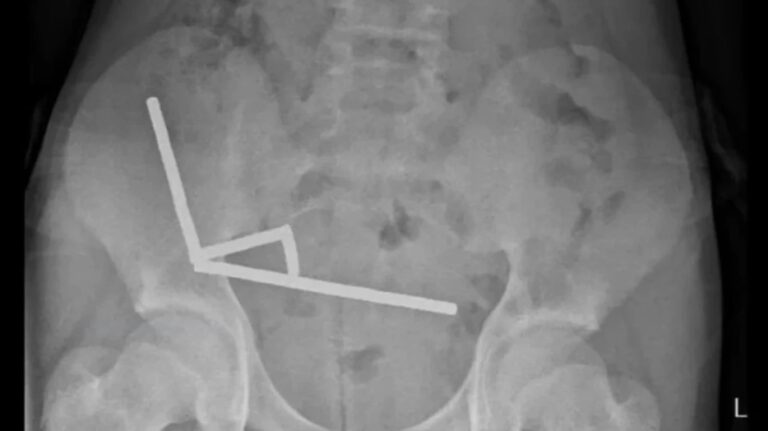

Η ακτινογραφία έδειξε ότι οι μαγνήτες είχαν συσσωρευτεί σε τέσσερις ευθείες γραμμές μέσα στα έντερα του παιδιού. Βρίσκονταν σε ξεχωριστά μέρη του εντέρου και είχαν κολλήσει μεταξύ τους λόγω μαγνητικών δυνάμεων.

Οι γιατροί ανέφεραν ότι η πίεση των μαγνητών είχε προκαλέσει νέκρωση σε τέσσερα σημεία του λεπτού εντέρου και του τυφλού εντέρου του αγοριού, το οποίο αποτελεί μέρος του παχέος εντέρου. Οι χειρουργοί επενέβησαν για να αφαιρέσουν τον νεκρό ιστό και να ανακτήσουν τους μαγνήτες.